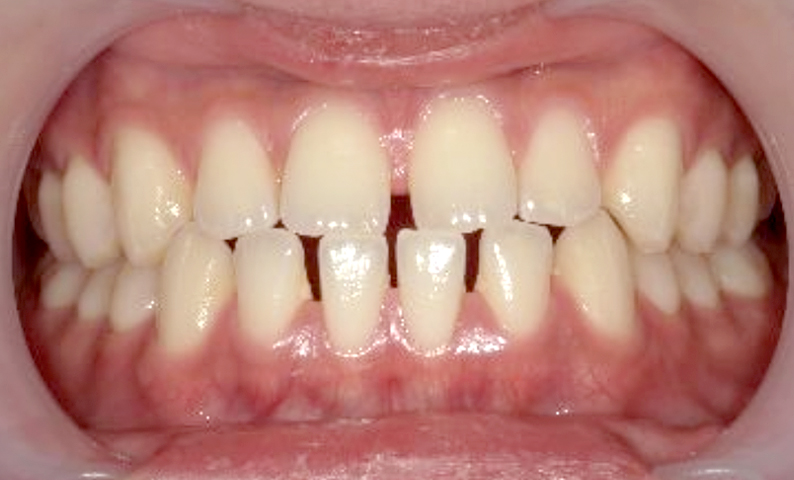

| 治療前 | 治療後 |

|---|---|

|